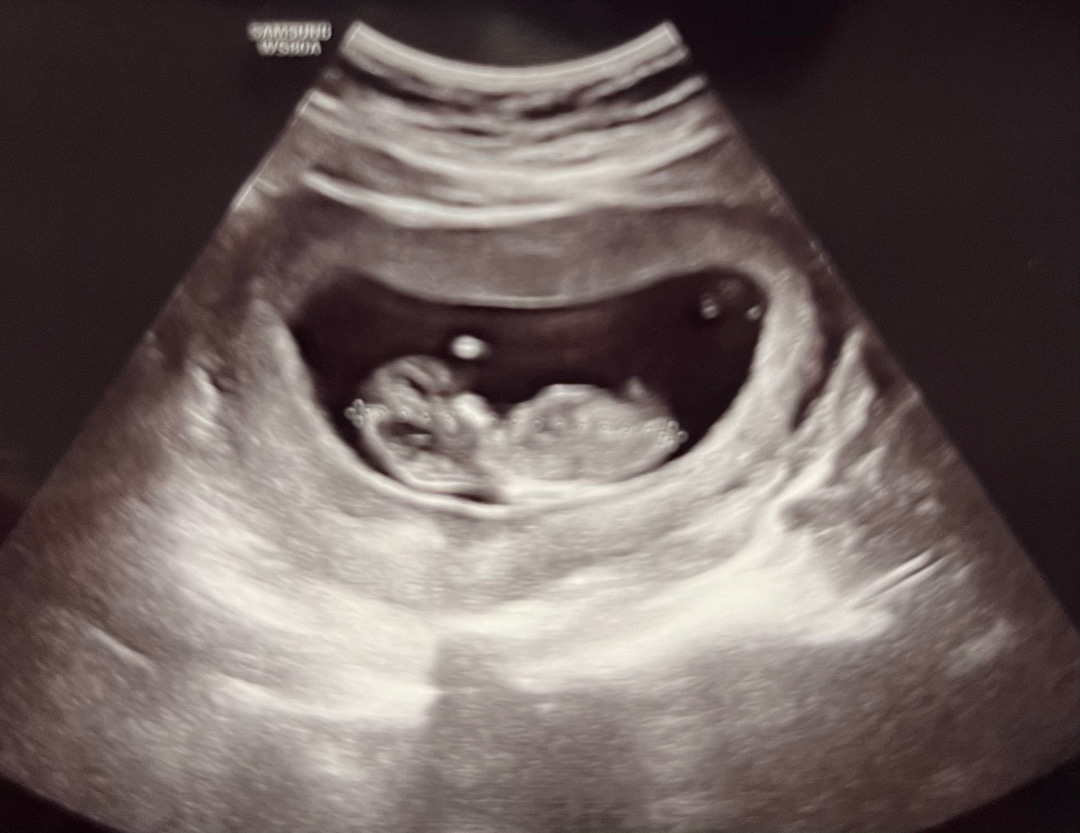

초음파 한번만 봐주세요 ㅎㅎ

오늘이 딱 12주 되는 날인데요! 아들같은 느낌인데 혹시 맞을까요...?

이 각도론 성별을 알 수 없어용

다른 사진은 없을까용??